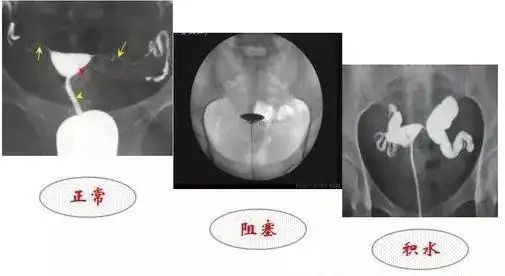

学会自己看输卵管造影片

教你如何看懂输卵管堵塞粘连积水造影片子